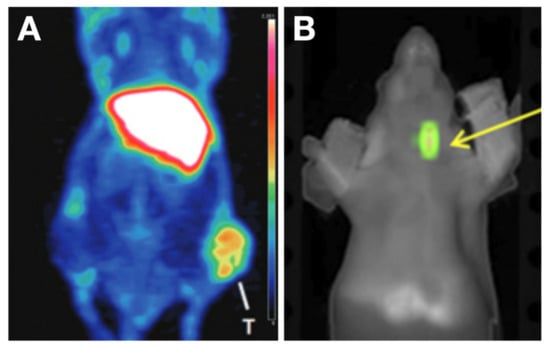

- Wei, W.; Jiang, D.; Rosenkrans, Z.T.; Barnhart, T.E.; Engle, J.W.; Luo, Q.; Cai, W. HER2-Targeted Multimodal Imaging of Anaplastic Thyroid Cancer. Am. J. Cancer Res. 2019, 9, 2413–2427. [Google Scholar]